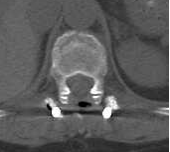

▲术后复查胸腰椎正侧位片提示:脊柱序列恢复,骨折椎体形态高度完全恢复,内固定位置满意。